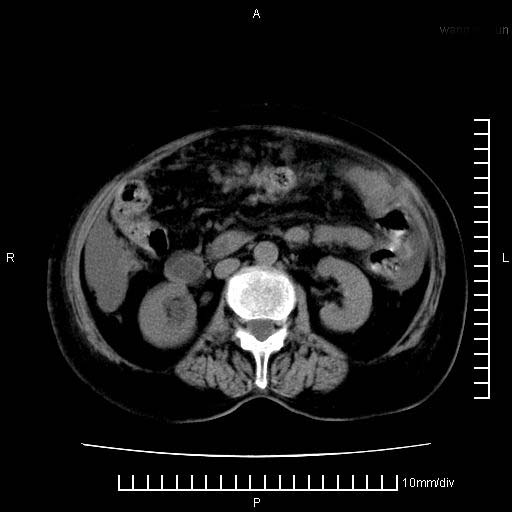

标题: CT28280:腹部增强:女性,80岁

上腹疼痛月余,外院核磁诊断胰腺癌。现临床示右下腹可明显触及包块,可片子上怎么没有看到?

胰腺结构模糊,胰尾部见囊性包块,周围脂肪密度增高,左肾前筋膜增厚,胸水、腹水。不符合胰腺ca伴腹膜腔转移。考虑胰腺炎伴假性囊肿形成、胸腹腔积液。

右肾盂囊肿。

1)考虑胰腺癌并胰腺假性囊肿形成。2)肝内低密度灶,不排除转移。3)右肾盂积水。4)腹水。5)右侧胸腔积液并右肺下叶部分膨胀不全。